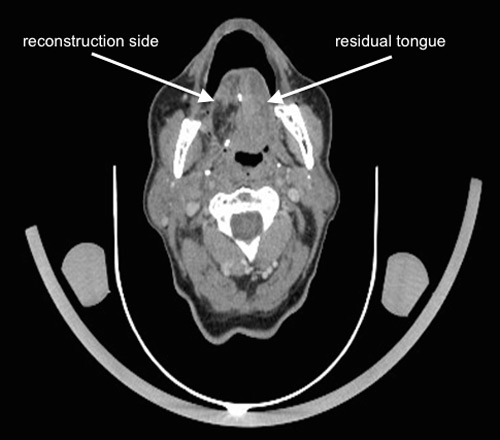

Figure 2

Follow-up contrast enhanced computed tomography part from a 18F-FDG-PET/CT scan 6 months following right partial glossectomy, elective neck dissection and reconstruction of the tongue with a radial forearm free flap for a pT2 pN1 squamous cell carcinoma. The primary site cannot be evaluated exactly regarding local recurrence. There are no evident suspicious lymph nodes to be detected.

After all there is no consensus of the perfect time for baseline and follow-up imaging. At our institution first imaging will be done 10 weeks after treatment. After that follow-up imaging is based on the previous findings. Since locoregional recurrence is often seen during the first two years after initial treatment the authors feel there is a legitimate reason for another subsequent scan, e.g., after 12, and 24 months. 18F-FDG-PET/CT is shown to be more accurate than conventional follow-up imaging alone regarding the detection rate of recurrences (fig. 2, and 3) [68]. Any additional imaging modalities should be performed on clinical signs. Suspicious lymph nodes can best be evaluated with USgFNAC.